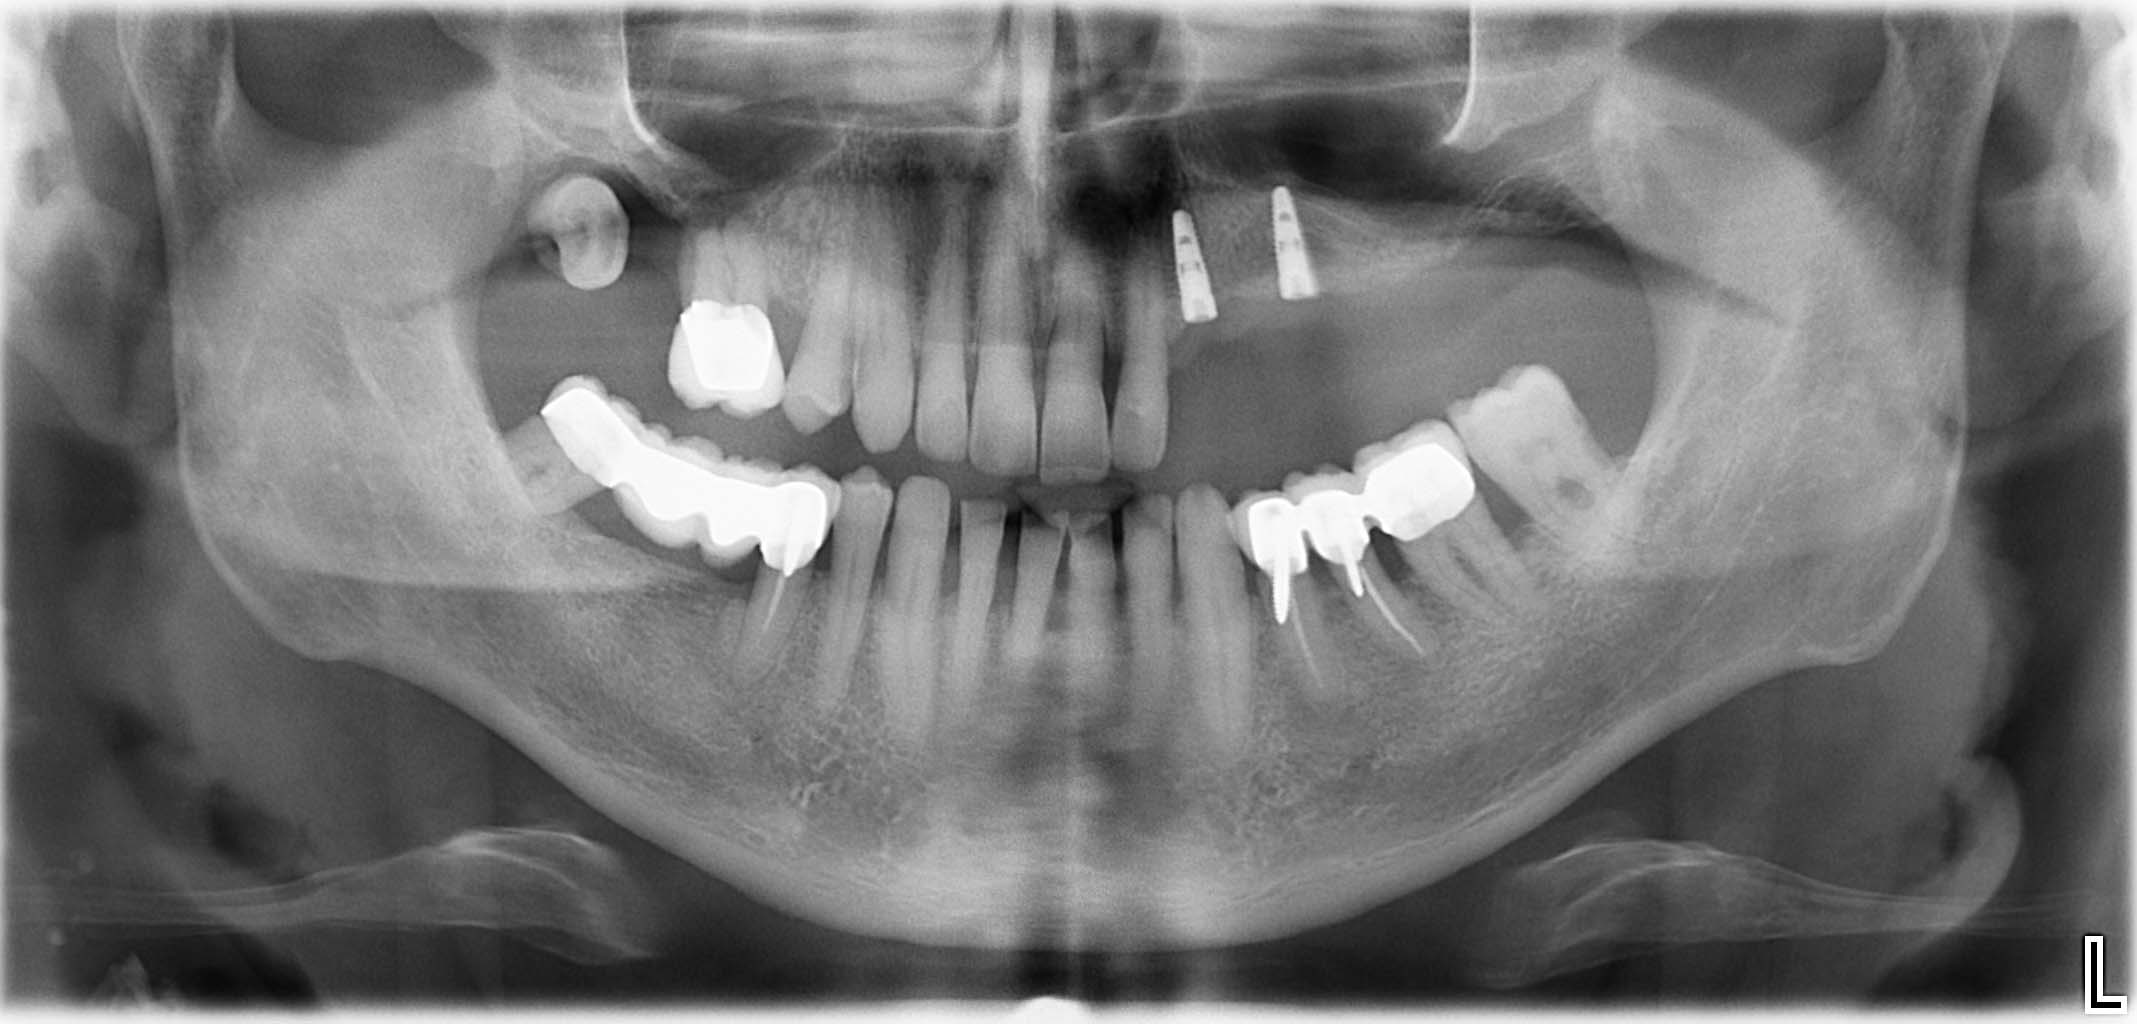

Ausgangssituation: Zahn 36 mit apikaler Beherdung, nicht erhaltungswürdig

Erfolgreich implantierte Patientenfälle (klinische Fotos)